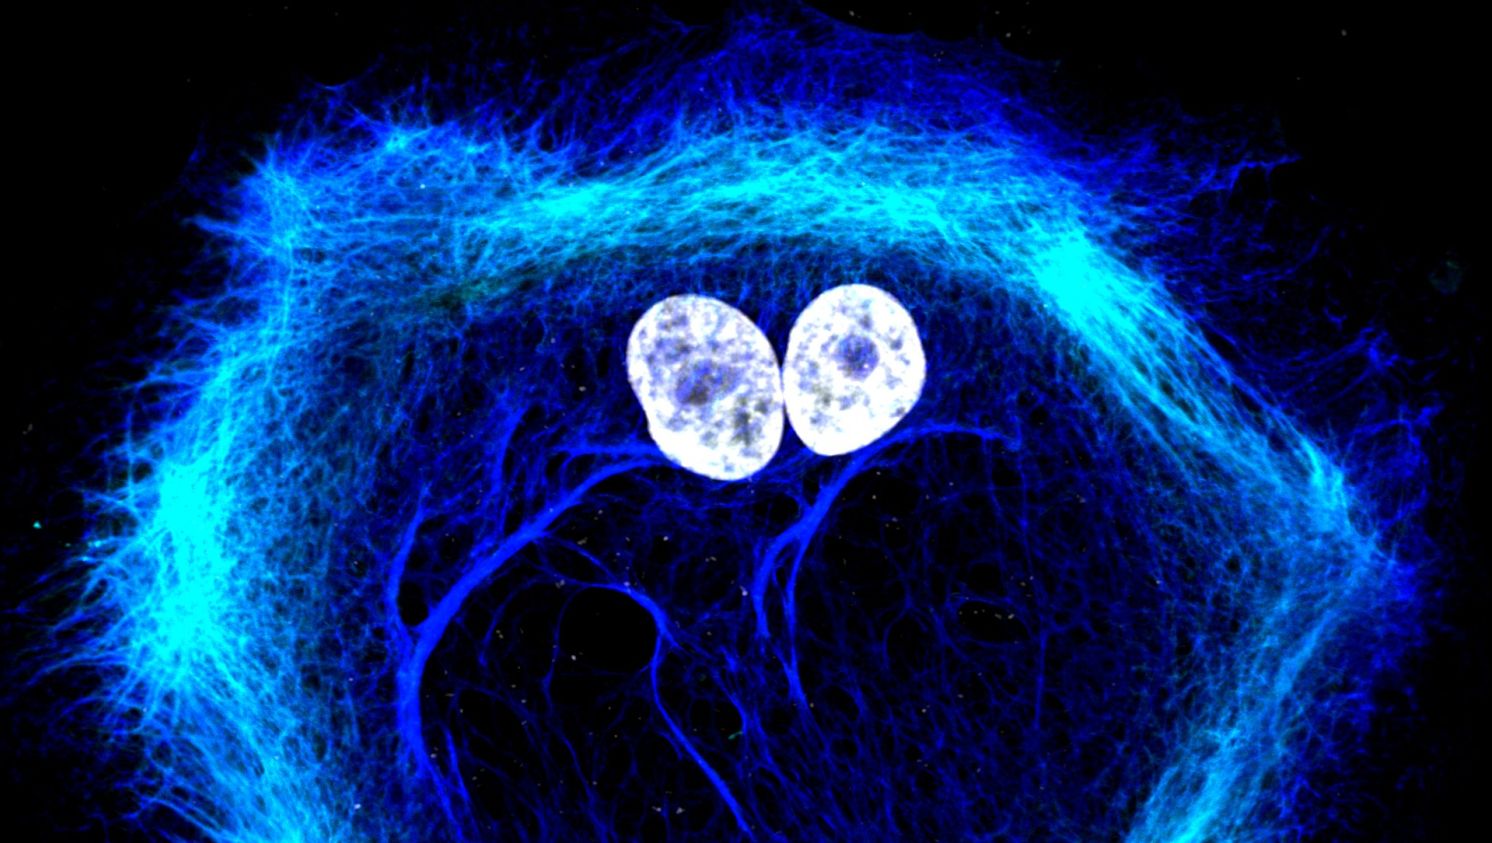

Nejjednodušeji se nanočástice pozorují pomocí fluorescenčního značení. Pokud zbarvíme jejich povrch nebo vnitřek, můžeme sledovat jejich pohyb uvnitř buněk nebo uvnitř tkání laboratorních myší.